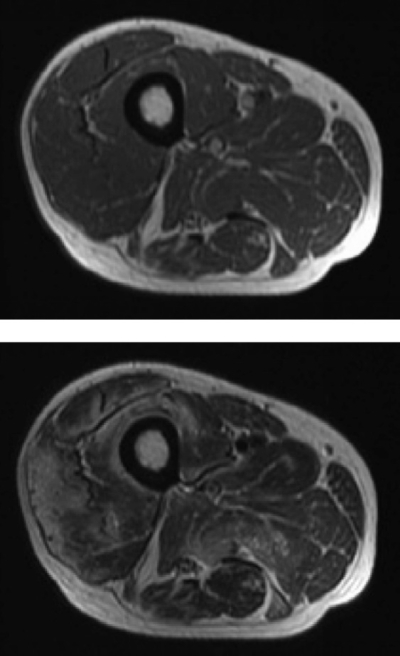

検査所見:血液所見:赤血球 504 万、Hb 15.8 g/dL、Ht 45 %、白血球 7,700、血小板 35 万。血液生化学所見:総蛋白 7.2 g/dL、アルブミン 3.3 g/dL、総ビリルビン 0.6 mg/dL、AST 96 U/L、ALT 112 U/L、CK 2,380 U/L(基準 30〜140)、Na 139 mEq/L、K 4.3 mEq/L、Cl 108 mEq/L。胸腹部 CT に異常を認めない。右大腿腿部 MRI の T1 強調像と T2 強調像とを別に示す。